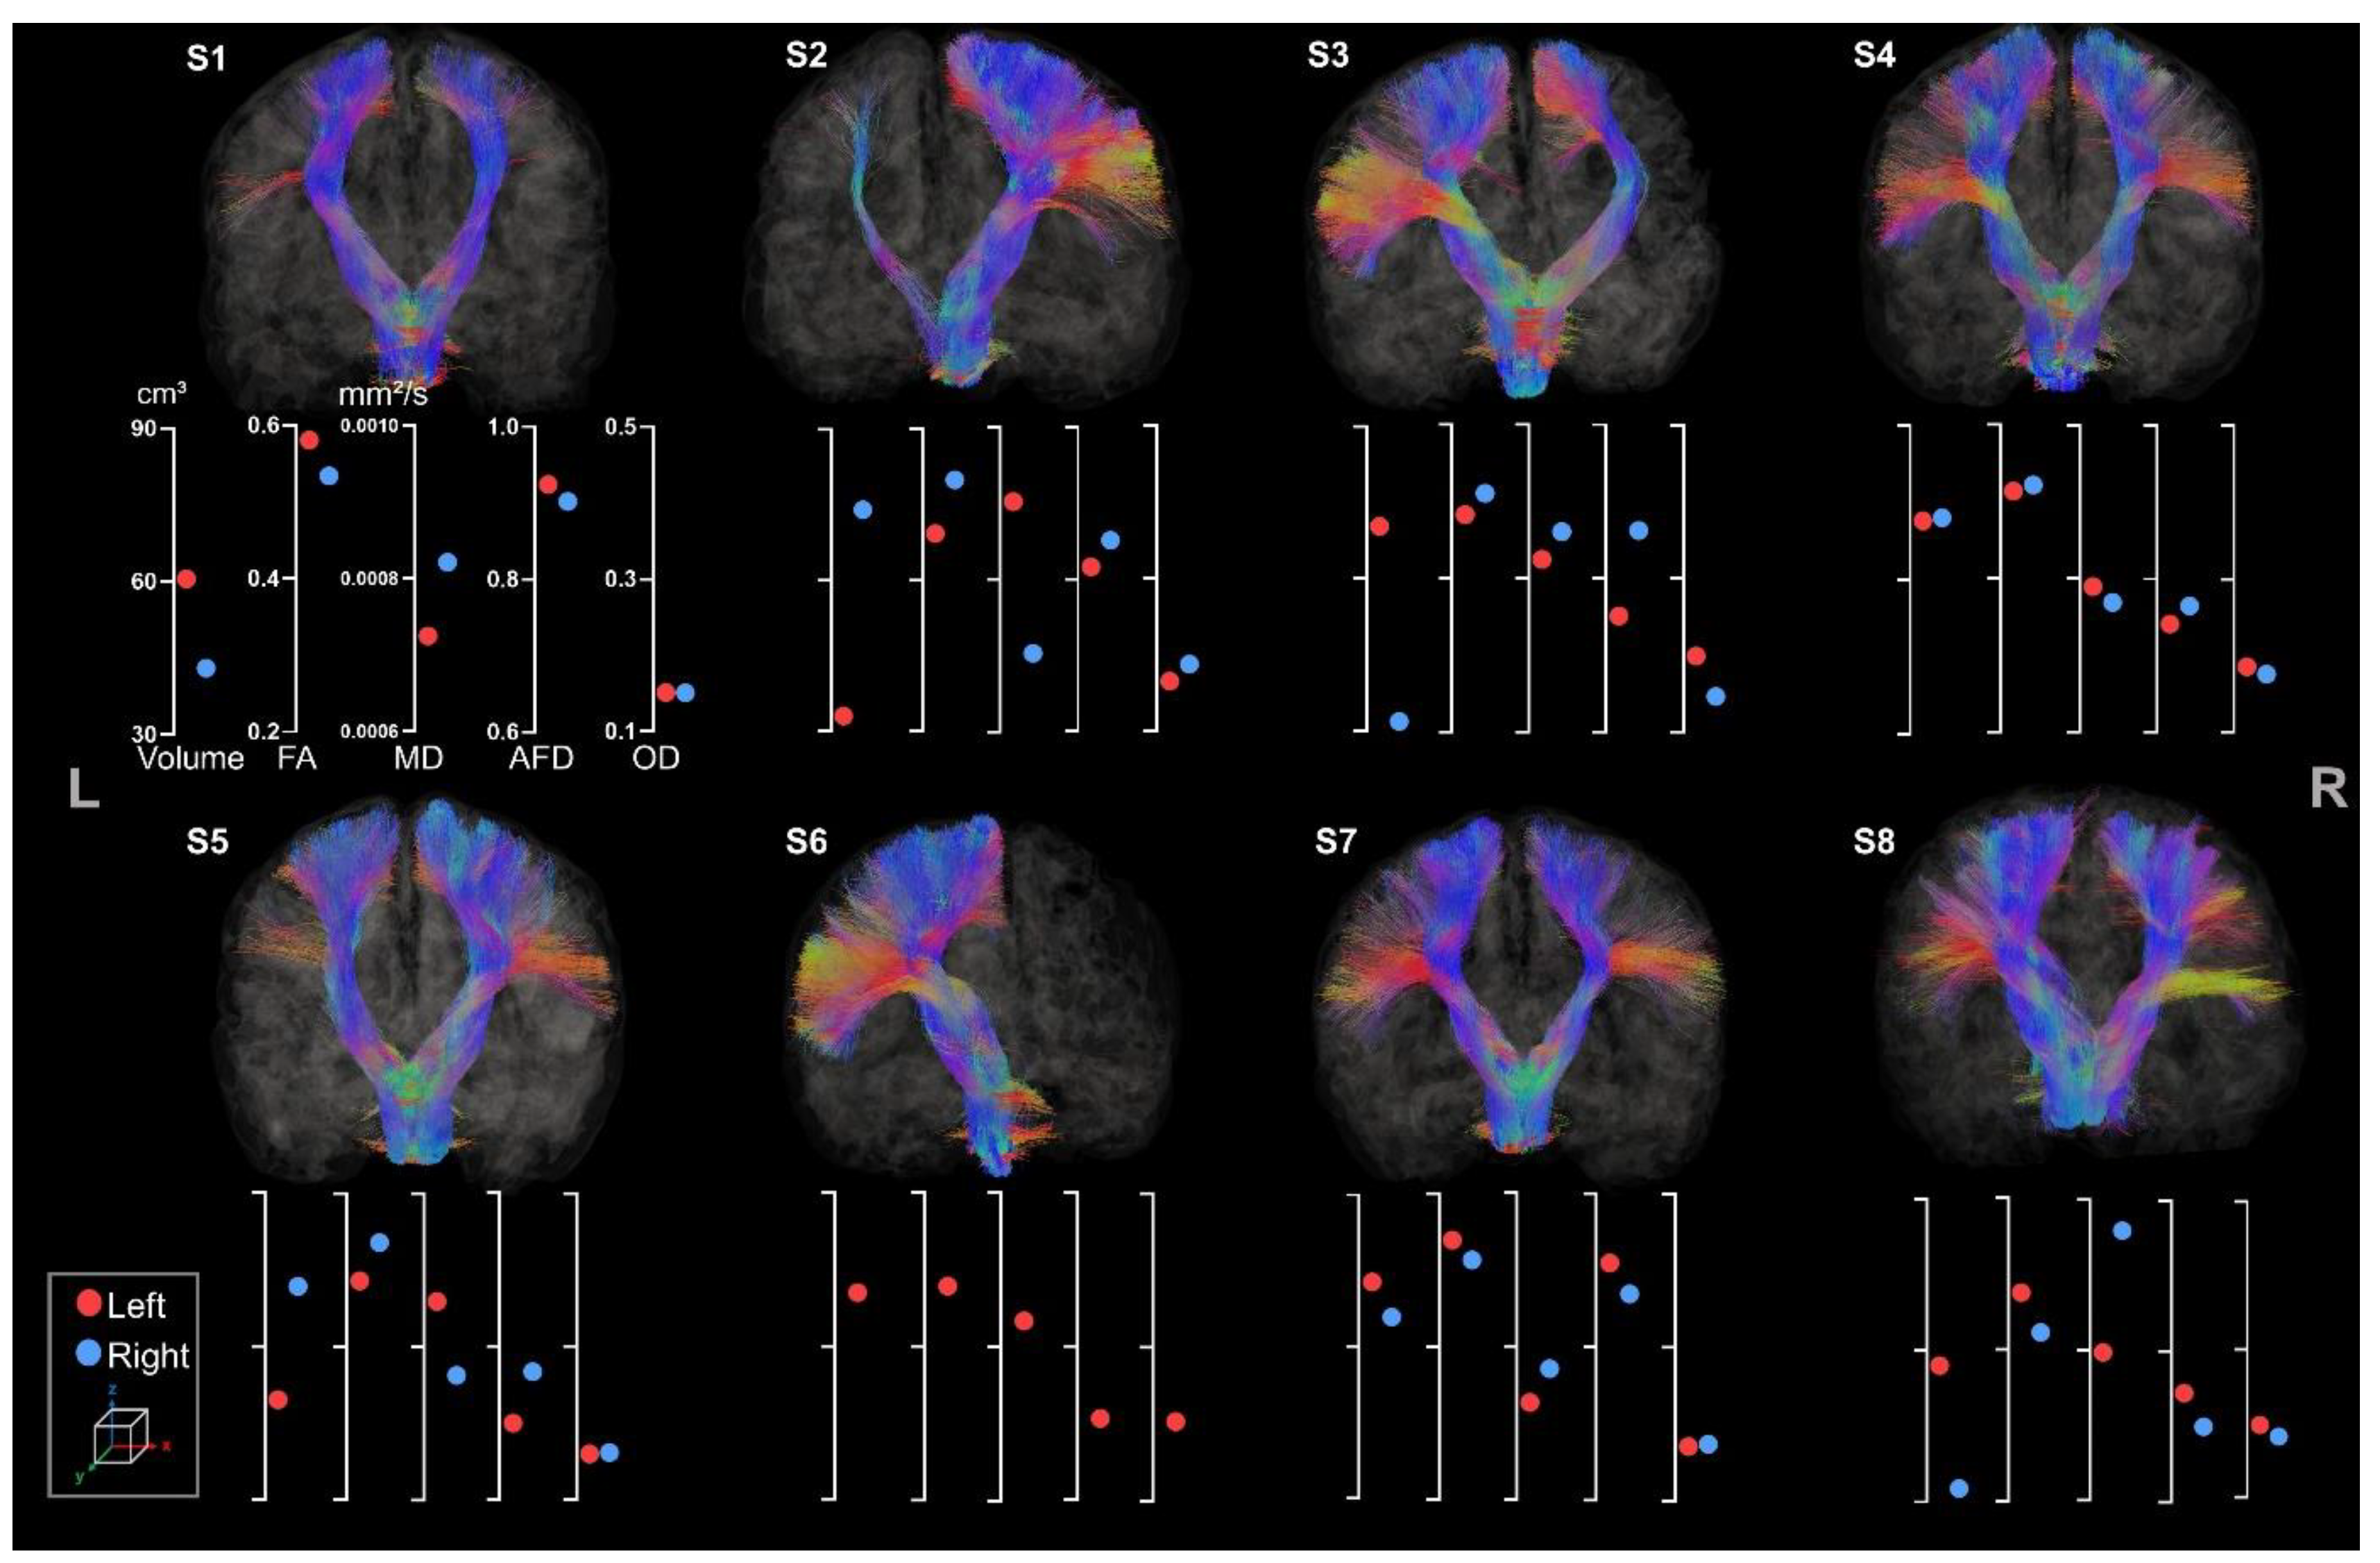

3.2.1. Corticospinal Tracts

3.2.2. Corpus Callosum